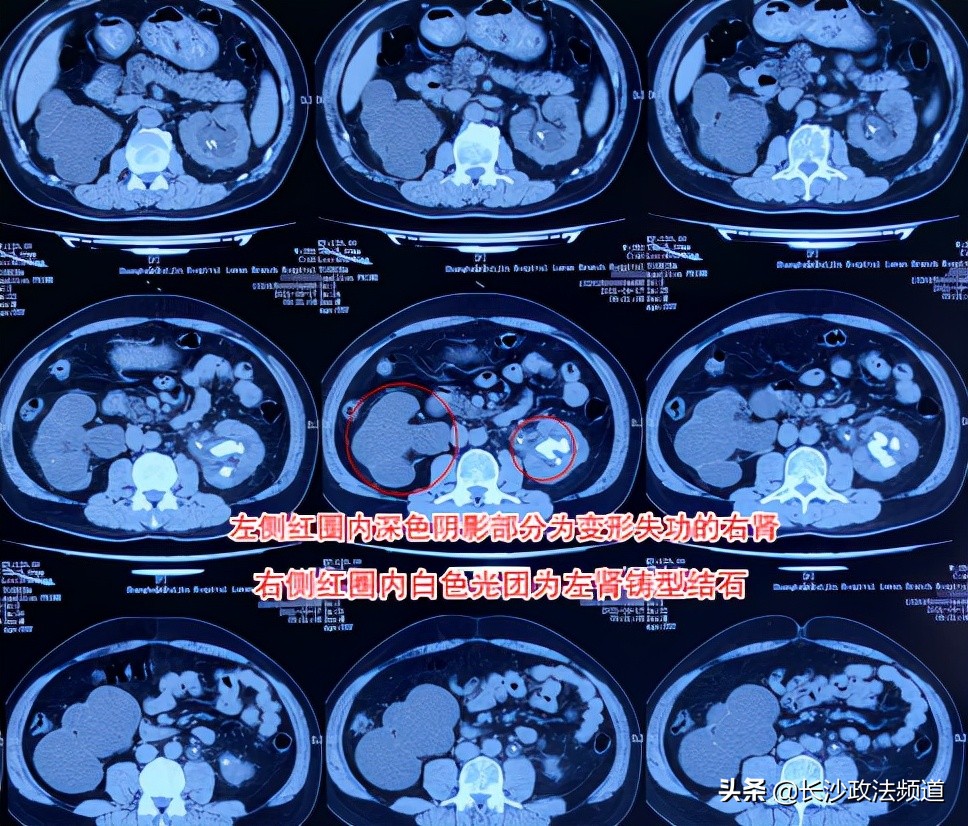

张先生术前CT检查结果局部图

10月27日,张先生顺利办理入院后,接受了详细的术前检查,确诊患有左肾铸型结石32*13mm、左输尿管上段结石、左肾积水,左肾陷入危机,必须尽早处理。

由于张先生的右肾已萎缩无功能,仅剩的保命左肾必须慎重对待。长沙京石医院副院长、泌尿外科主任卢卓雄介绍:“从患者的检查结果可以看到,右肾重度积水,肾实质非常薄,或者说基本上没有肾实质了,已经没有功能了,左肾肾盏积水加上铸形结石布满了整个肾脏,再不处理的话,这个肾脏也会坏掉,那就是尿毒症了,只能做肾移植。”